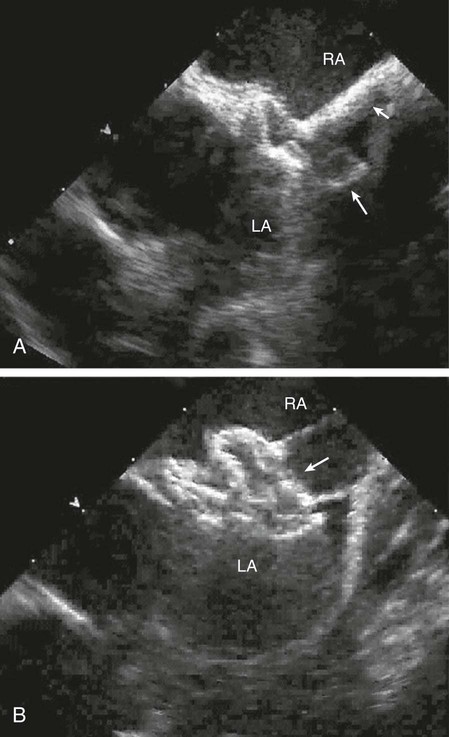

The echocardiogram (Fig. 426-6) is diagnostic and shows signs of right ventricular enlargement with encroachment of the mitral valve echo on the left ventricular outflow tract; the abnormally low position of the AV valves results in a “gooseneck” deformity of the left ventricular outflow tract. In normal hearts, the tricuspid valve inserts slightly more toward the apex than the mitral valve does. In AV septal defects, both valves insert at the same level because of absence of the AV septum. In complete AV septal defects, the ventricular septum is also deficient and the common AV valve is readily appreciated. Pulsed and color flow Doppler echocardiography will demonstrate left-to-right shunting at the atrial, ventricular, or left ventricular to right atrial levels and can be used to semiquantitate the degree of AV valve insufficiency. Echocardiography is useful for determining the insertion points of the chordae of the common AV valve and for evaluating the presence of associated lesions such as patent ductus arteriosus (PDA) or coarctation of the aorta.